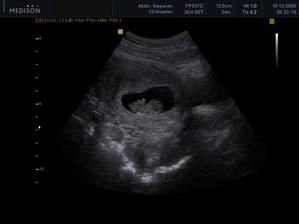

......bude to klučík.....